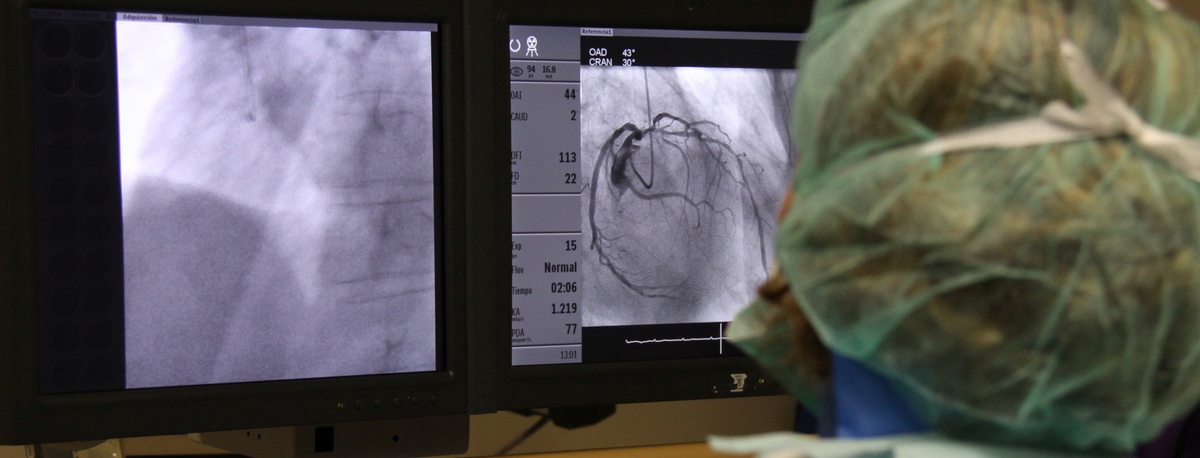

Angiologia, cirurgia vascular i endovascular

A l'institut comptem amb especialistes en angiologia, cirurgia vascular i endovascular per al diagnòstic i seguiment de les malalties de l'aparell circulatori. L'embòlia cerebral i el tromboembolisme pulmonar són algunes de les causes principals de mort deguda a un problema vascular.

El nostre equip és especialista en tècniques mínimament invasives, utilitzant tècniques endovasculars, sense cirurgia, que permeten implantar pròtesis vasculars per resoldre dilatacions o aneurismes de les artèries. També oferim tots els tractaments de la patologia venosa i arterial perifèrica, incloent-hi les malalties de les artèries caròtides.